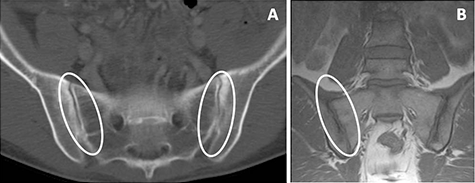

La sacroileítis radiológica (inflamación de la articulación situada entre el hueso sacro y el ilíaco) silente o asintomática, está presente en un 20% de los pacientes con EII. La prueba diagnóstica básica en estos caso es la radiología de pelvis y en algunas ocasiones, la resonancia magnética (RM) (Imagen 1).